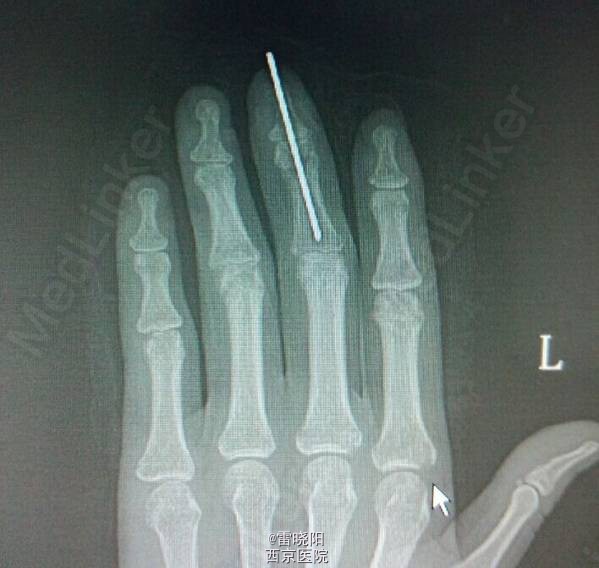

手指贯通伤

患者女,31岁。工作时不慎被药物压片机压伤左手1天